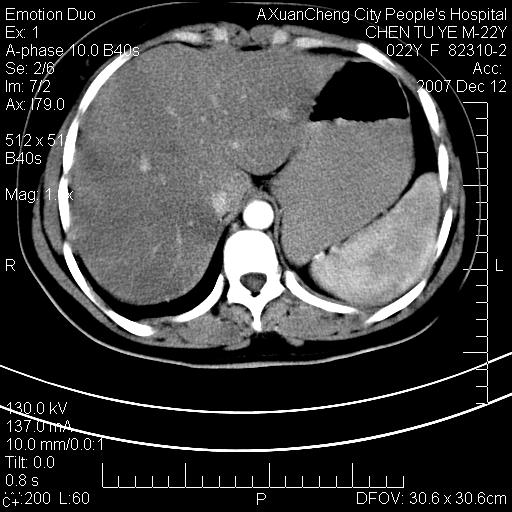

超声提示肝右前叶占位,约2.5cm.

各位战友看看病灶在什么地方,可是右前叶进肝裂部低密度影,平扫ct值约10以下,增强后增高明显

1 脾大,慢性肝损伤. 2 肝脏脂肪侵润.  3 你所指的部位疑点,我没看出有问题.

脂肪肝.楼主所指部位不考虑异常,为肝圆韧带影.

不均匀脂肪浸润,版主所说的病灶为肝园韧带服着点。